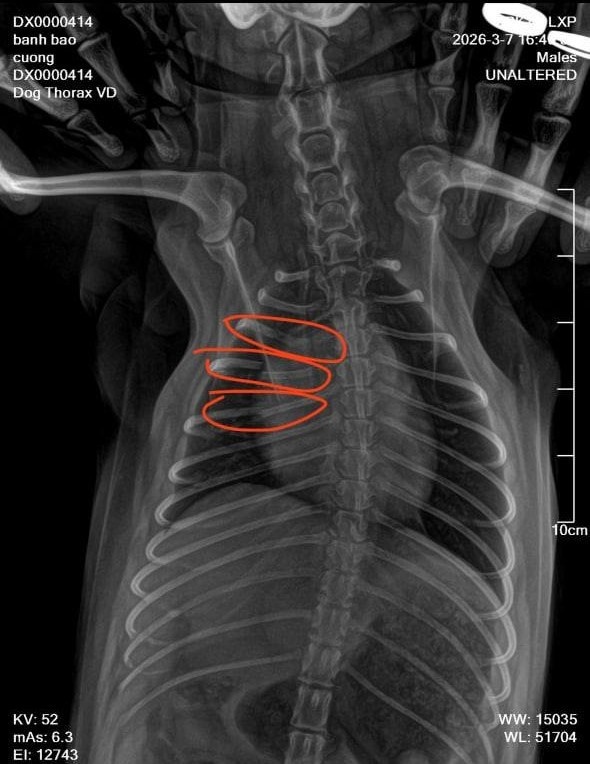

"Lúc đó trong tiệm không có ai cả, vợ tôi cũng ra ngoài. Tầm 15 phút sau vợ tôi trở về thì thấy chú chó kêu gào đau đớn nên đưa tới phòng khám thú y. Kết quả chụp phim cho thấy chú chó bị gãy tới 3 xương sườn. Vì chó cưng của tôi nhỏ quá nên bác sĩ bảo không thể bó bột được, chỉ đợi tự liền xương và phục hồi", anh xót xa.

| Chú chó phốc sóc bị gãy 3 xương sườn. |